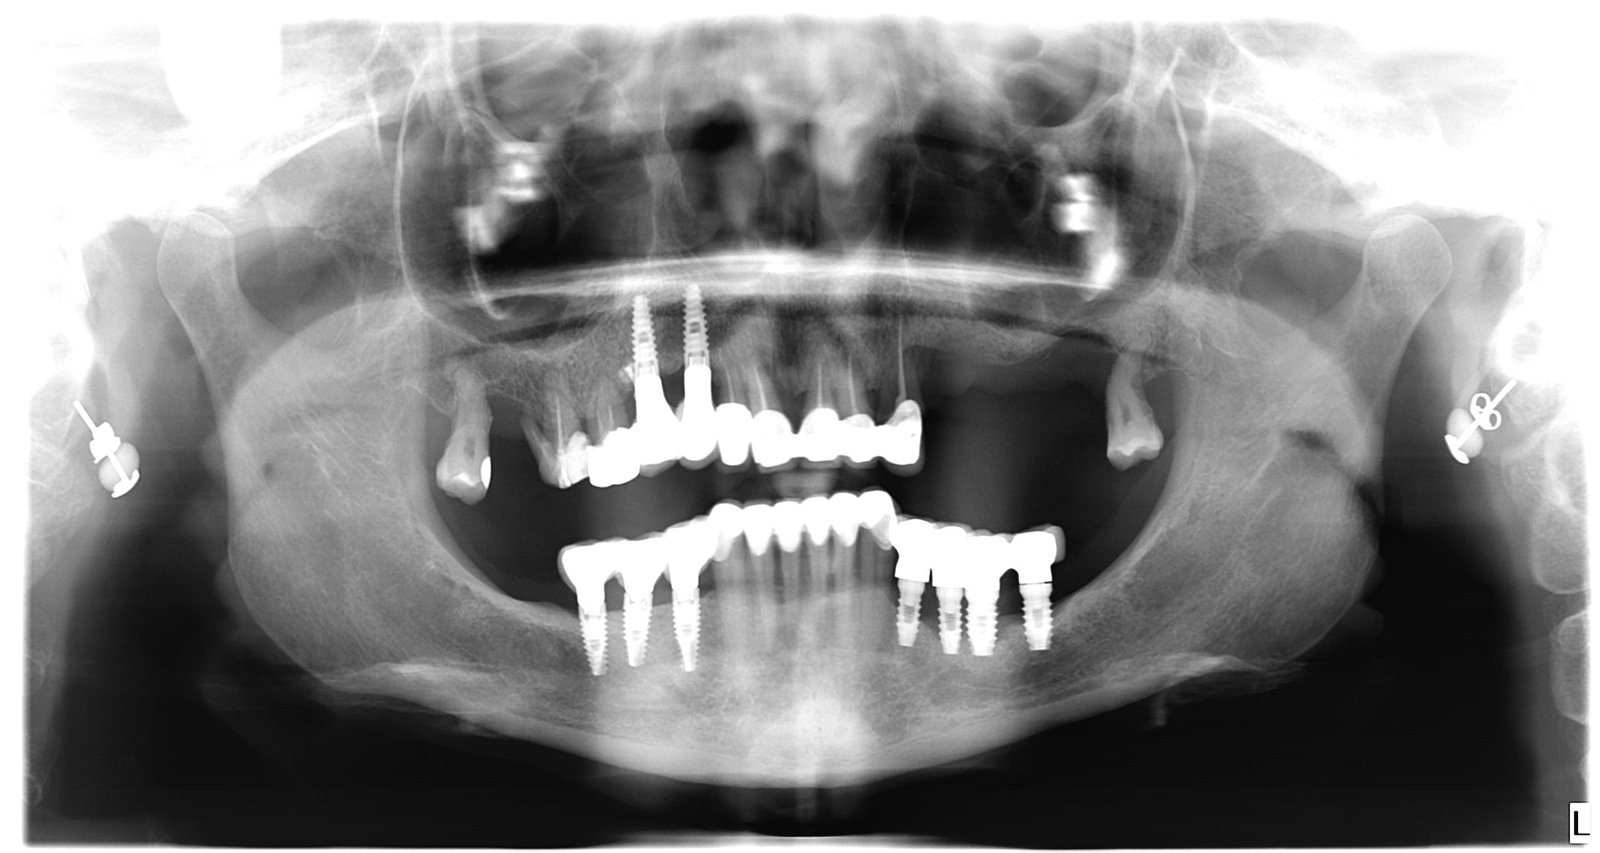

Caso 1 - caso de Implantes dentales

El paciente acudió a consulta con la ausencia de varias piezas dentales que dificultaban la masticación y afectaban a la estética de su sonrisa. Con la colocación de implantes dentales conseguimos recuperar dientes fijos, funcionales y de aspecto natural, devolviéndole seguridad y comodidad al sonreír.

En esta imagen se aprecia la ausencia de piezas dentales y el estado inicial del hueso, lo que permitió planificar un tratamiento implantológico preciso y seguro.